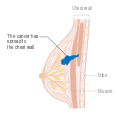

يمكن أن تؤدي الأورام الخبيثة إلى أورام نقيلية - أورام ثانوية (تنشأ من الورم الرئيسي) تنتشر إلى ما بعد مكان نشأتها. تعتمد الأعراض التي يسببها سرطان الثدي النقيلي على موقع الورم الخبيث. تشمل المواقع الشائعة للورم الخبيث العظام والكبد والرئة والمخ.[34] عندما يصل السرطان إلى مثل هذه الحالة الغازية، يتم تصنيفه على أنه سرطان من المرحلة الرابعة، وغالبًا ما تكون سرطانات هذه الحالة قاتلة.[35] تشمل الأعراض الشائعة لسرطان المرحلة الرابعة فقدان الوزن غير المبرر وآلام العظام والمفاصل واليرقان والأعراض العصبية. تسمى هذه الأعراض أعراض غير محددة لأنها يمكن أن تكون مظاهر لأمراض أخرى كثيرة.[36] نادرًا ما ينتشر سرطان الثدي إلى مواقع غير شائعة جدًا مثل العقد الليمفاوية المحيطة بالبنكرياس مما يؤدي إلى انسداد القنوات الصفراوية مما يؤدي إلى صعوبات في التشخيص.[37]

- المرحلة: مراحل سرطان الثدي باستخدام نظام TNM يعتمد على حجم tumor (T) "الورم" سواء أكان أم لم يكن منتشراً إلى العقد nodes (N) اللمفاوية تحت الإبط، أو كان الورم metastasized (M) "منتشراً" (أي منتشر لأكثر من مكان في الجسم). حجم أكبر، انتشار عقدي، والورم الخبيث له رقم مرحلة أكبر ومآل أسوأ.

- المرحلة 4: هو السرطان "النقيلي" الذي له مآل أقل مواتاة لانتشاره خارج الثدي والغدد الليمفاوية الإقليمية.

مرحلة سرطان الثدي هي أهم عنصر في طرق التصنيف التقليدية لسرطان الثدي، لأن لها تأثير أكبر على المآل من الاعتبارات الأخرى. يأخذ تقييم المرحلة في الاعتبار الحجم والتوغل الموضعي وحالة العقدة الليمفاوية وما إذا كان المرض المنتشر موجودًا. كلما تقدمت مرحلة التشخيص، كان التشخيص سيئاً. تتقدم المرحلة لتوغل المرض في لغدد الليمفاوية وجدار الصدر والجلد أو ما بعده، ولعدوانية الخلايا السرطانية. تتراجع المرحلة لوجود مناطق خالية من السرطان وسلوك الخلية القريب من الطبيعي (الدرجات). الحجم ليس عاملاً في تحديد المرحلة ما لم يكن السرطان غازيًا. على سبيل المثال، سرطان القنوات الموضعي (DCIS) الذي يشمل الثدي بالكامل سيظل في المرحلة صفر وبالتالي يكون التشخيص ممتاز مع البقاء بدون مرض لمدة 10 سنوات بنسبة 98% تقريبًا.[169]

- المرحلة 4، السرطان النقيلي (أي الذي ينتشر إلى أماكن أبعد)، مآله سيء، ويدار من خلال مجموعة متنوعة من جميع العلاجات الجراحية والإشعاعية والكيميائية والعلاجات المستهدفة. معدل البقاء على قيد الحياة لعشر سنوات يبلغ 5% بدون علاج و10% بالعلاج الأمثل.[171]